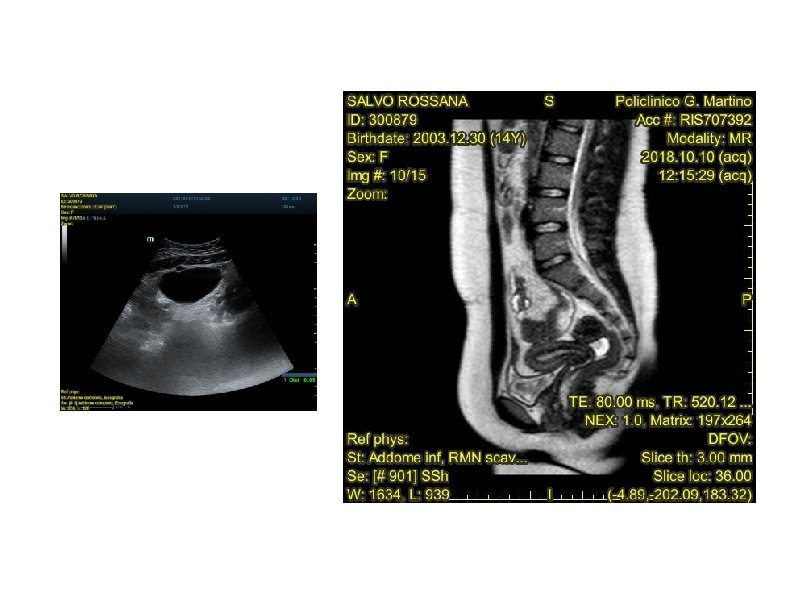

CASO CLINICO Ragazza di 15 anni con dolore in regione sopraombelicale da circa due settimane Due mesi prima, sottoposta ad appendicectomia videolaparoscopica (DT 7 mm, raccolta periappendicolare) Esami urine ed esami ematochimici nella norma E. O. : addome trattabile, dolenzia in regione ipogastrica senza resistenza